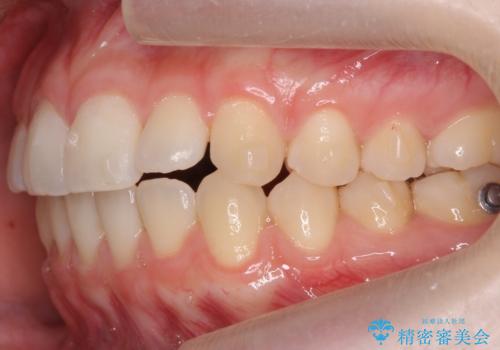

咬んでも向こう側が見える、前歯が閉じない症状でした。また、上の前歯が少し前に出ている状態でした。

上の前歯をわずかに削る処置を行い、後ろに下げながら下の歯となるべく咬むように矯正治療を行いました。